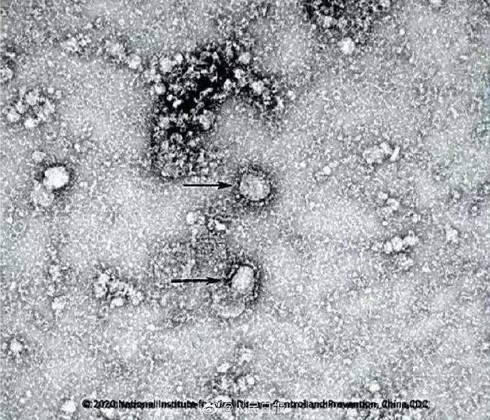

Hình ảnh coronavirus trên kính hiển vi. Ảnh: RIA.

Theo báo cáo của Viện Doherty tại Melbourne, virus được nuôi cấy từ một mẫu bệnh phẩm. Đây là trường hợp đầu tiên nuôi cấy được chủng coronavirus này bên ngoài Trung Quốc.